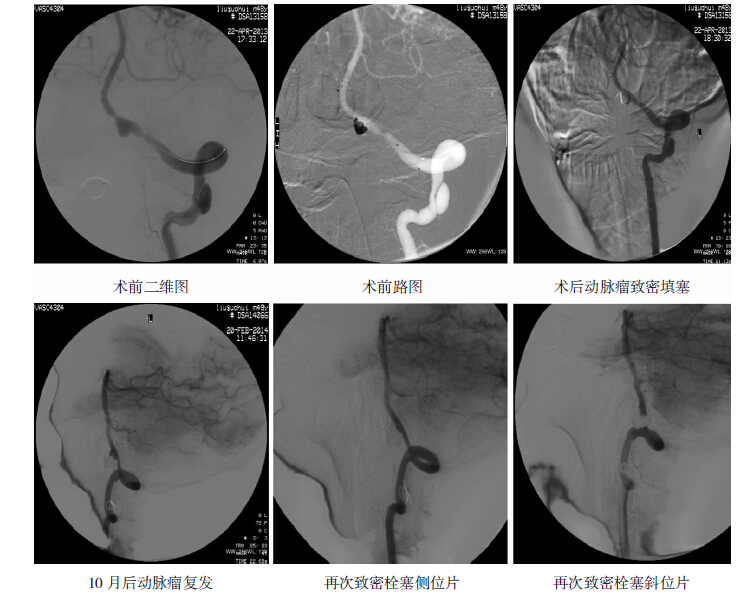

在行血管内治疗前均先行全脑血管内造影,仔细评价夹层动脉瘤的形态及部位、夹层动脉瘤与载瘤动脉及小脑后下动脉(PICA)的关系、夹层动脉瘤是否位于优势侧椎动脉,以此制定手术方案。本组病人术中使用支架为:Enterprise 支架(Cordis 公司)或Solitaire (EV3) 支架。植入支架后,病人术中肝素化,术后口服氯吡格雷(75 mg/d) 3 个月,拜阿司匹林(100 mg/d)6月,所有病人均于术后3~18个月获得临床随访和/或影像学随访。 2 结果 2.1 支架辅助弹簧圈治疗组(附一例病人影像学资料见图 1)

17例病人行支架辅助弹簧圈栓塞夹层动脉瘤,其中9例病人致密填塞动脉瘤,载瘤动脉通畅,8例大部分栓塞动脉瘤,载瘤动脉通畅。术后随访,9例致密栓塞者见1例动脉瘤复发(见图 2),予以再次行栓塞治疗,其余8例未见复发,均无出血及缺血表现。行球囊或弹簧圈闭塞椎动脉组:6例患者夹层动脉瘤均位于非优势侧,对侧代偿良好,术后随访均未见动脉瘤复发,未出现出血及缺血症状。行单纯支架置入术组:均为未破裂出血动脉瘤,12例行支架置入中有8例行单支架,术后随访,动脉瘤均处于稳定中,未见明显缩小及增大。另外4例行双支架重叠置入,术后随访,见1例动脉瘤明显缩小,造影剂滞留。另2例未见变化。观察组:6例未出血动脉瘤且未处理夹层动脉瘤者,6月~1年后随访见4例无明显变化,2例明显增大,遂行支架辅助弹簧圈填塞术,术中致密填塞。术后随访未见复发。(不同血管内治疗的效果见表 1)

| 图 1 支架辅助弹簧圈栓塞动脉瘤 |

| 图 2 动脉瘤行手术后复发再次手术 |